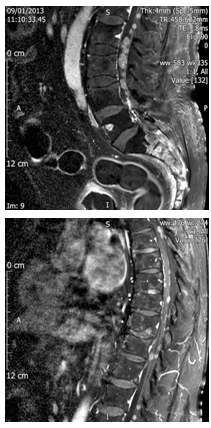

5 months later, the patient came to Emergency Services with short-time evolution of functional impotence and strength loss in both legs. Neurologic exploration presented the next situation: higher neurological functions and cranial nerves inside normality, arms without deficit, strength loss 2/5 in left leg and 3/5 in right leg, preserved sensitivity, tendon reflexes preserved, and plantar reflex in flection. No pain touching or precutting sacrum, pelvis or lumbar spine. Neural-axis MRI study revealed bone metastasis in sacrum, already known, and leptomeningeal spread with tumor lesions dependent of intra-dural and outside spinal cord meningeal with some other lesions inside and outside spinal cord at thoracic level (Figures 2 & 3). In dural bag, nodular injury follows radicular (Figure 4). No new diagnostic tests were performed because of progressive disease nature.

Figure 2 & 3 Neural-axis MRI.

Figure 4 In dural bag, nodular injury follows radicular.

Continuing with our case analysis, in MRI thoracic cord lesions are described as suggestive of intra-spinal location (Figure 4). This fact seems very relevant according to two aspects. Firstly, in reviewed literature are described possible mechanisms of invasion that are present in solid tumors at higher levels in leptomeningeal location when beginning is sacrum, or blood spread or direct involvement of intra-dural extra-cord component5,10 which would explain our case. And secondly, this figure is not described in the reviewed literature in any prostate cancer, so we consider that is a singular fact different from the published ones before and, in our opinion, could be one step closer to progression of disease.